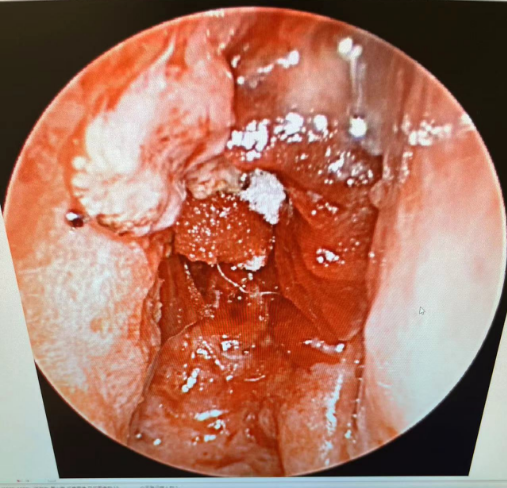

综合考虑后,蒋主任立即就给患者做了鼻内镜检查,并同时取了病理活检,内镜可见肿物已长满整个右侧鼻腔,伴少许黏稠鼻涕,已无通气空间,肿物表面呈白色荔枝肉样改变,乍一看确实很像“鼻息肉”。

▲鼻腔术后内镜

术中多点取材,避免漏诊可能性,最终病理提示:呼吸上皮乳头状瘤,部分呈内翻性生长,部分呈外生性生长,合并原位鳞状细胞癌,局灶见间质浸润。

患者术后反应轻微,麻醉苏醒后即精神恢复良好,术后第二天换药见黏膜瓣在位良好,可以明显减少术后窦口挛缩再闭锁可能。